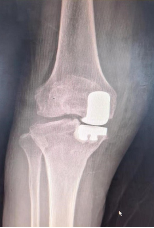

单髁置换术:随着骨科微创技术和快速康复理念发展,越来越多骨科医生倾向于微创手术方式。单髁置换术术中截骨量更少,手术创伤更小。不需要进行输血,从而感染率更低,住院时间更短,安全性更高,符合快速康复理念。在经过康复训练之后,更容易“遗忘”这次手术,运动更加协调自如。对于75岁以上符合适应症的高龄患者单髁置换术优势更加明显。

(单髁置换术后影像)